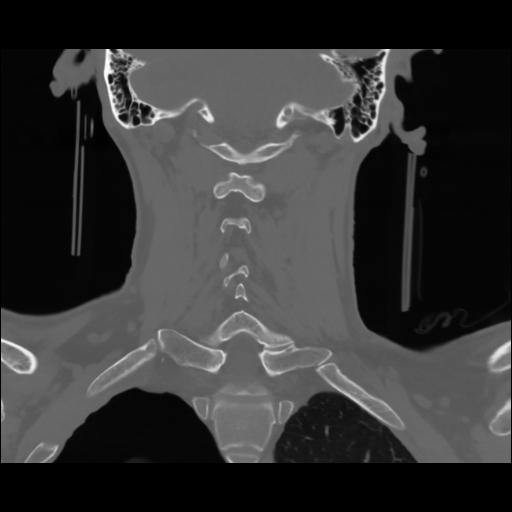

13 P.BLANDAS,,Coronal,2.000,P.BLANDAS,Coronal,